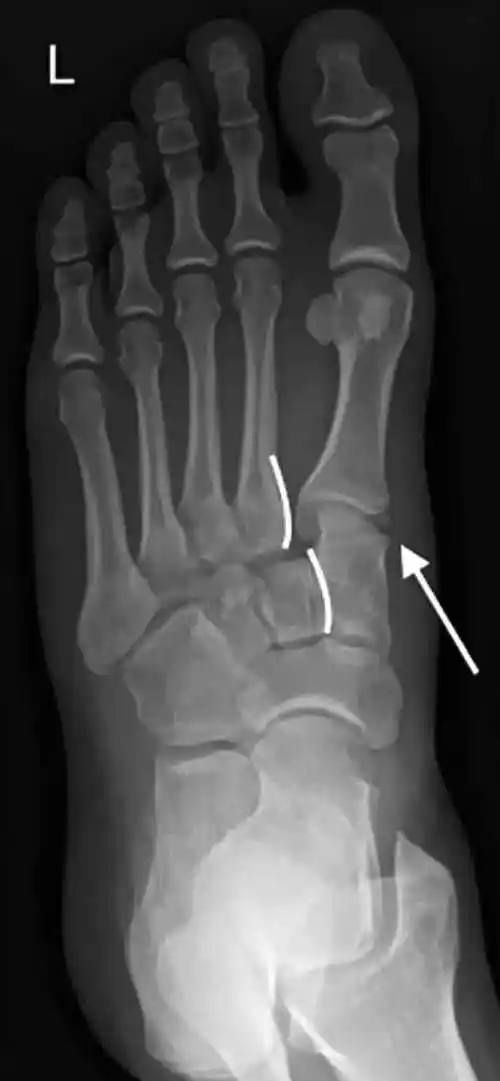

X 线是常用的初步检查手段,通过正位、斜位、侧位和应力位等不同角度拍摄 ,能观察各跖骨与楔骨的对齐情况。正位片上,要留意是否有 “斑点征”,这可能是撕脱骨折的表现,就像夜空中的异常亮点;斜位和侧位片能帮助评估关节对位及跖骨背侧移位情况,从不同视角揭示损伤秘密 。